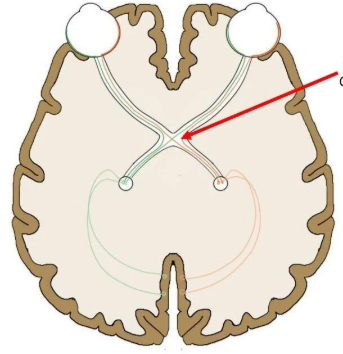

Optic Chiasm

A structure in the visual system that allows for one image to be created from both eyes.

Lateral Geniculate Nucleus (LGN)

A structure in the thalamus that is the relay/processing center for visual information.

Optic Radiations

A structure in the brain that transmits visual information from the LGN to the primary visual cortex.